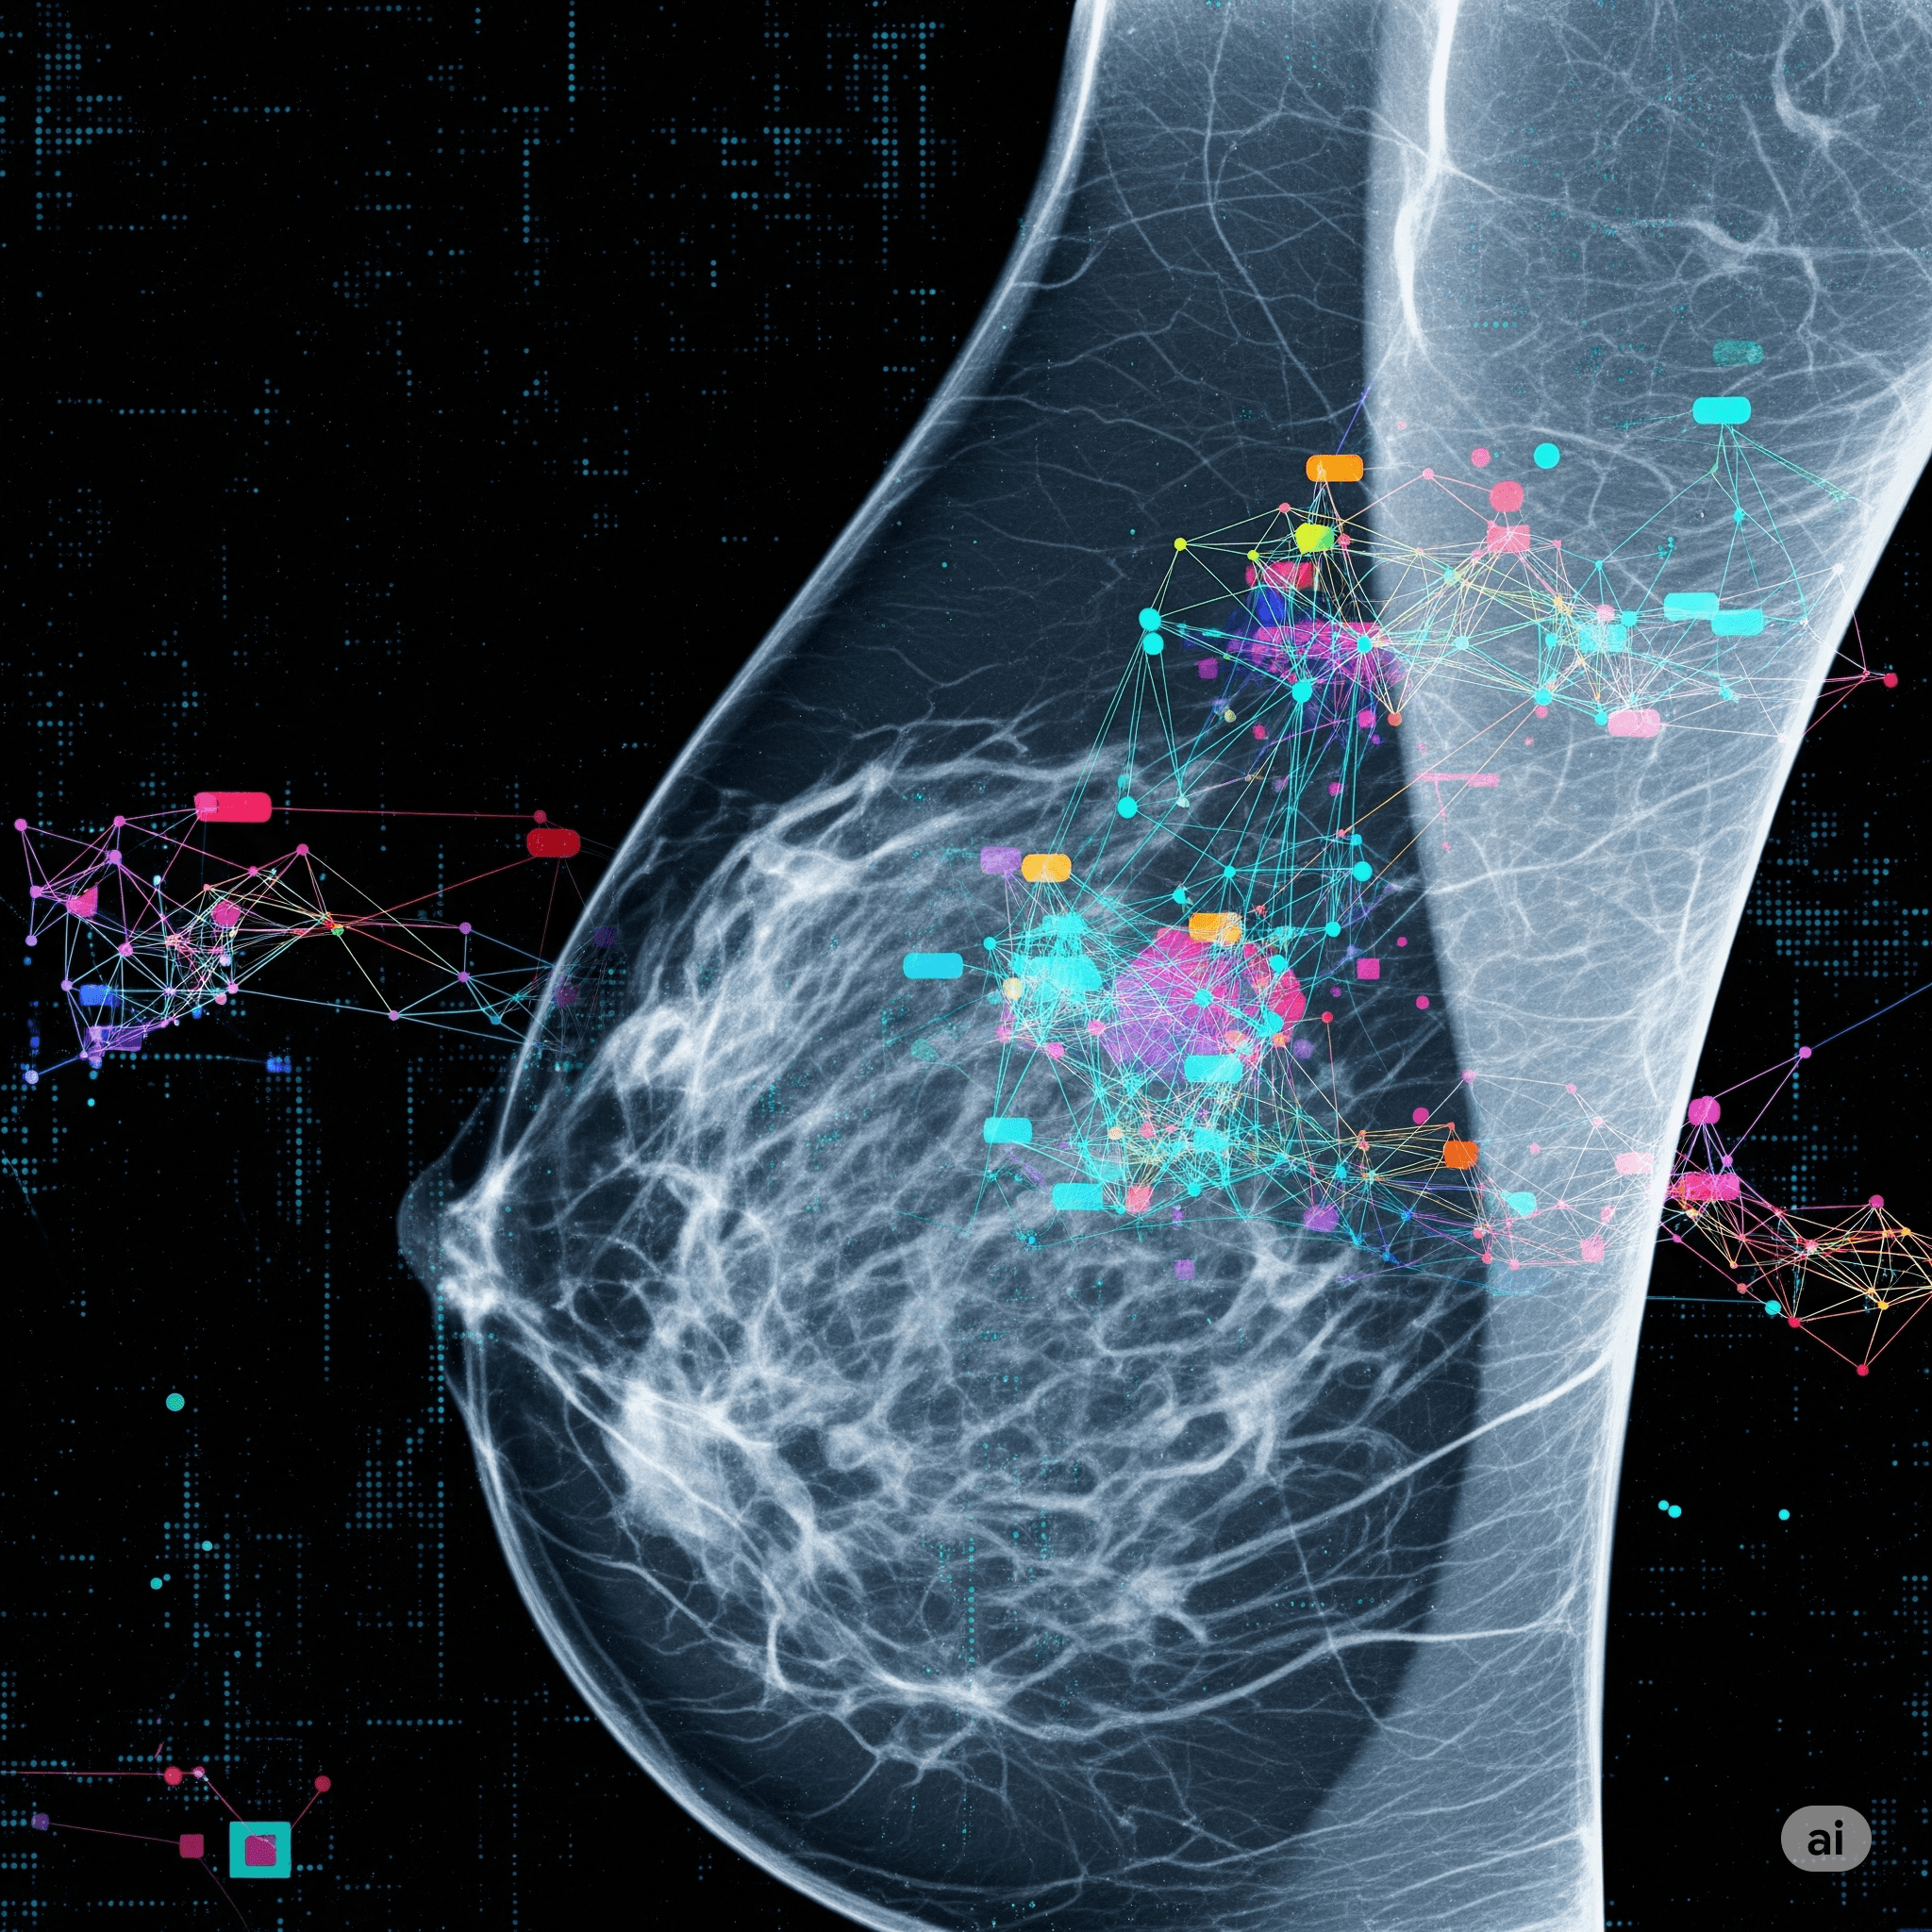

Machine Learning

Data Science

Machine Learning

Data Science